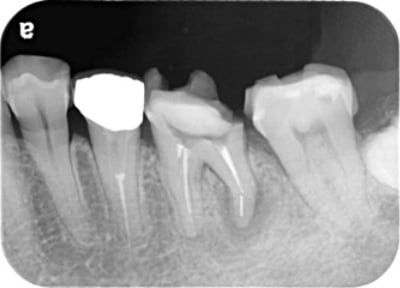

昔から噛んだ時に違和感があった。「噛み合わせが強いことが原因だろう」と言われ、削って噛み合わせの調整を何年も受けていた。詰め物が取れたことをきっかけに調べて来院。

歯の中を触ると膿がかなりでてきました。

根管の中が無菌に近い状態になるように洗浄を繰り返します。

根管の中を封鎖し、根管治療終了

根管治療が終わったところが、また隙間から感染しないように、

上から被せを精密に接着させ、密封。

治療後病気がなくなり骨が再生した